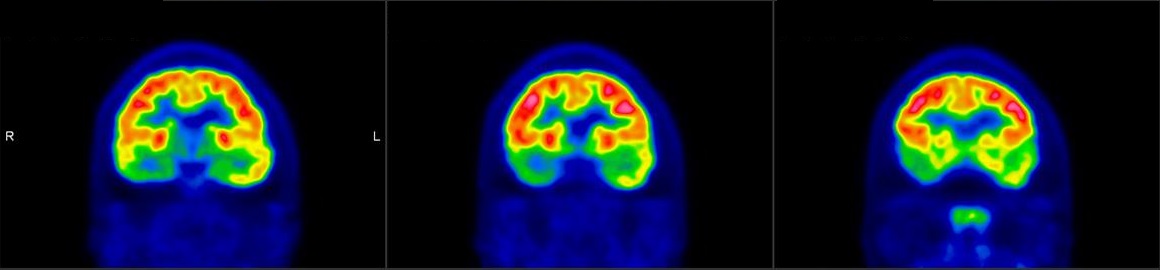

PET/CT scans with special tracers can show 3-dimensional images of blood flow and biomolecules deposition in the brain for diagnosis and monitoring the therapy progress of various neurological diseases, such as Alzheimer's, Dementia, Parkinson's disease, Huntingdon's chorea and autism. In 2018, the National Institute on Aging-Alzheimer's Association (NIA-AA) had revised the definition of Alzheimer's Disease (AD) from a syndrome diagnosed by a set of clinical criteria to a biological construct using abnormal protein deposits to define AD as a unique neurodegenerative disease that can lead to dementia. Our hospital has almost 20 years of experience in producing specific tracer to detect abnormal protein deposition in the brain.

- Epilepsy

For some types of epilepsy patients, PET/CT scans can localize the epilepsy-causing focus in the brain. Modern stereotaxic neurosurgery can then cure epilepsy permanently by excising the focus.